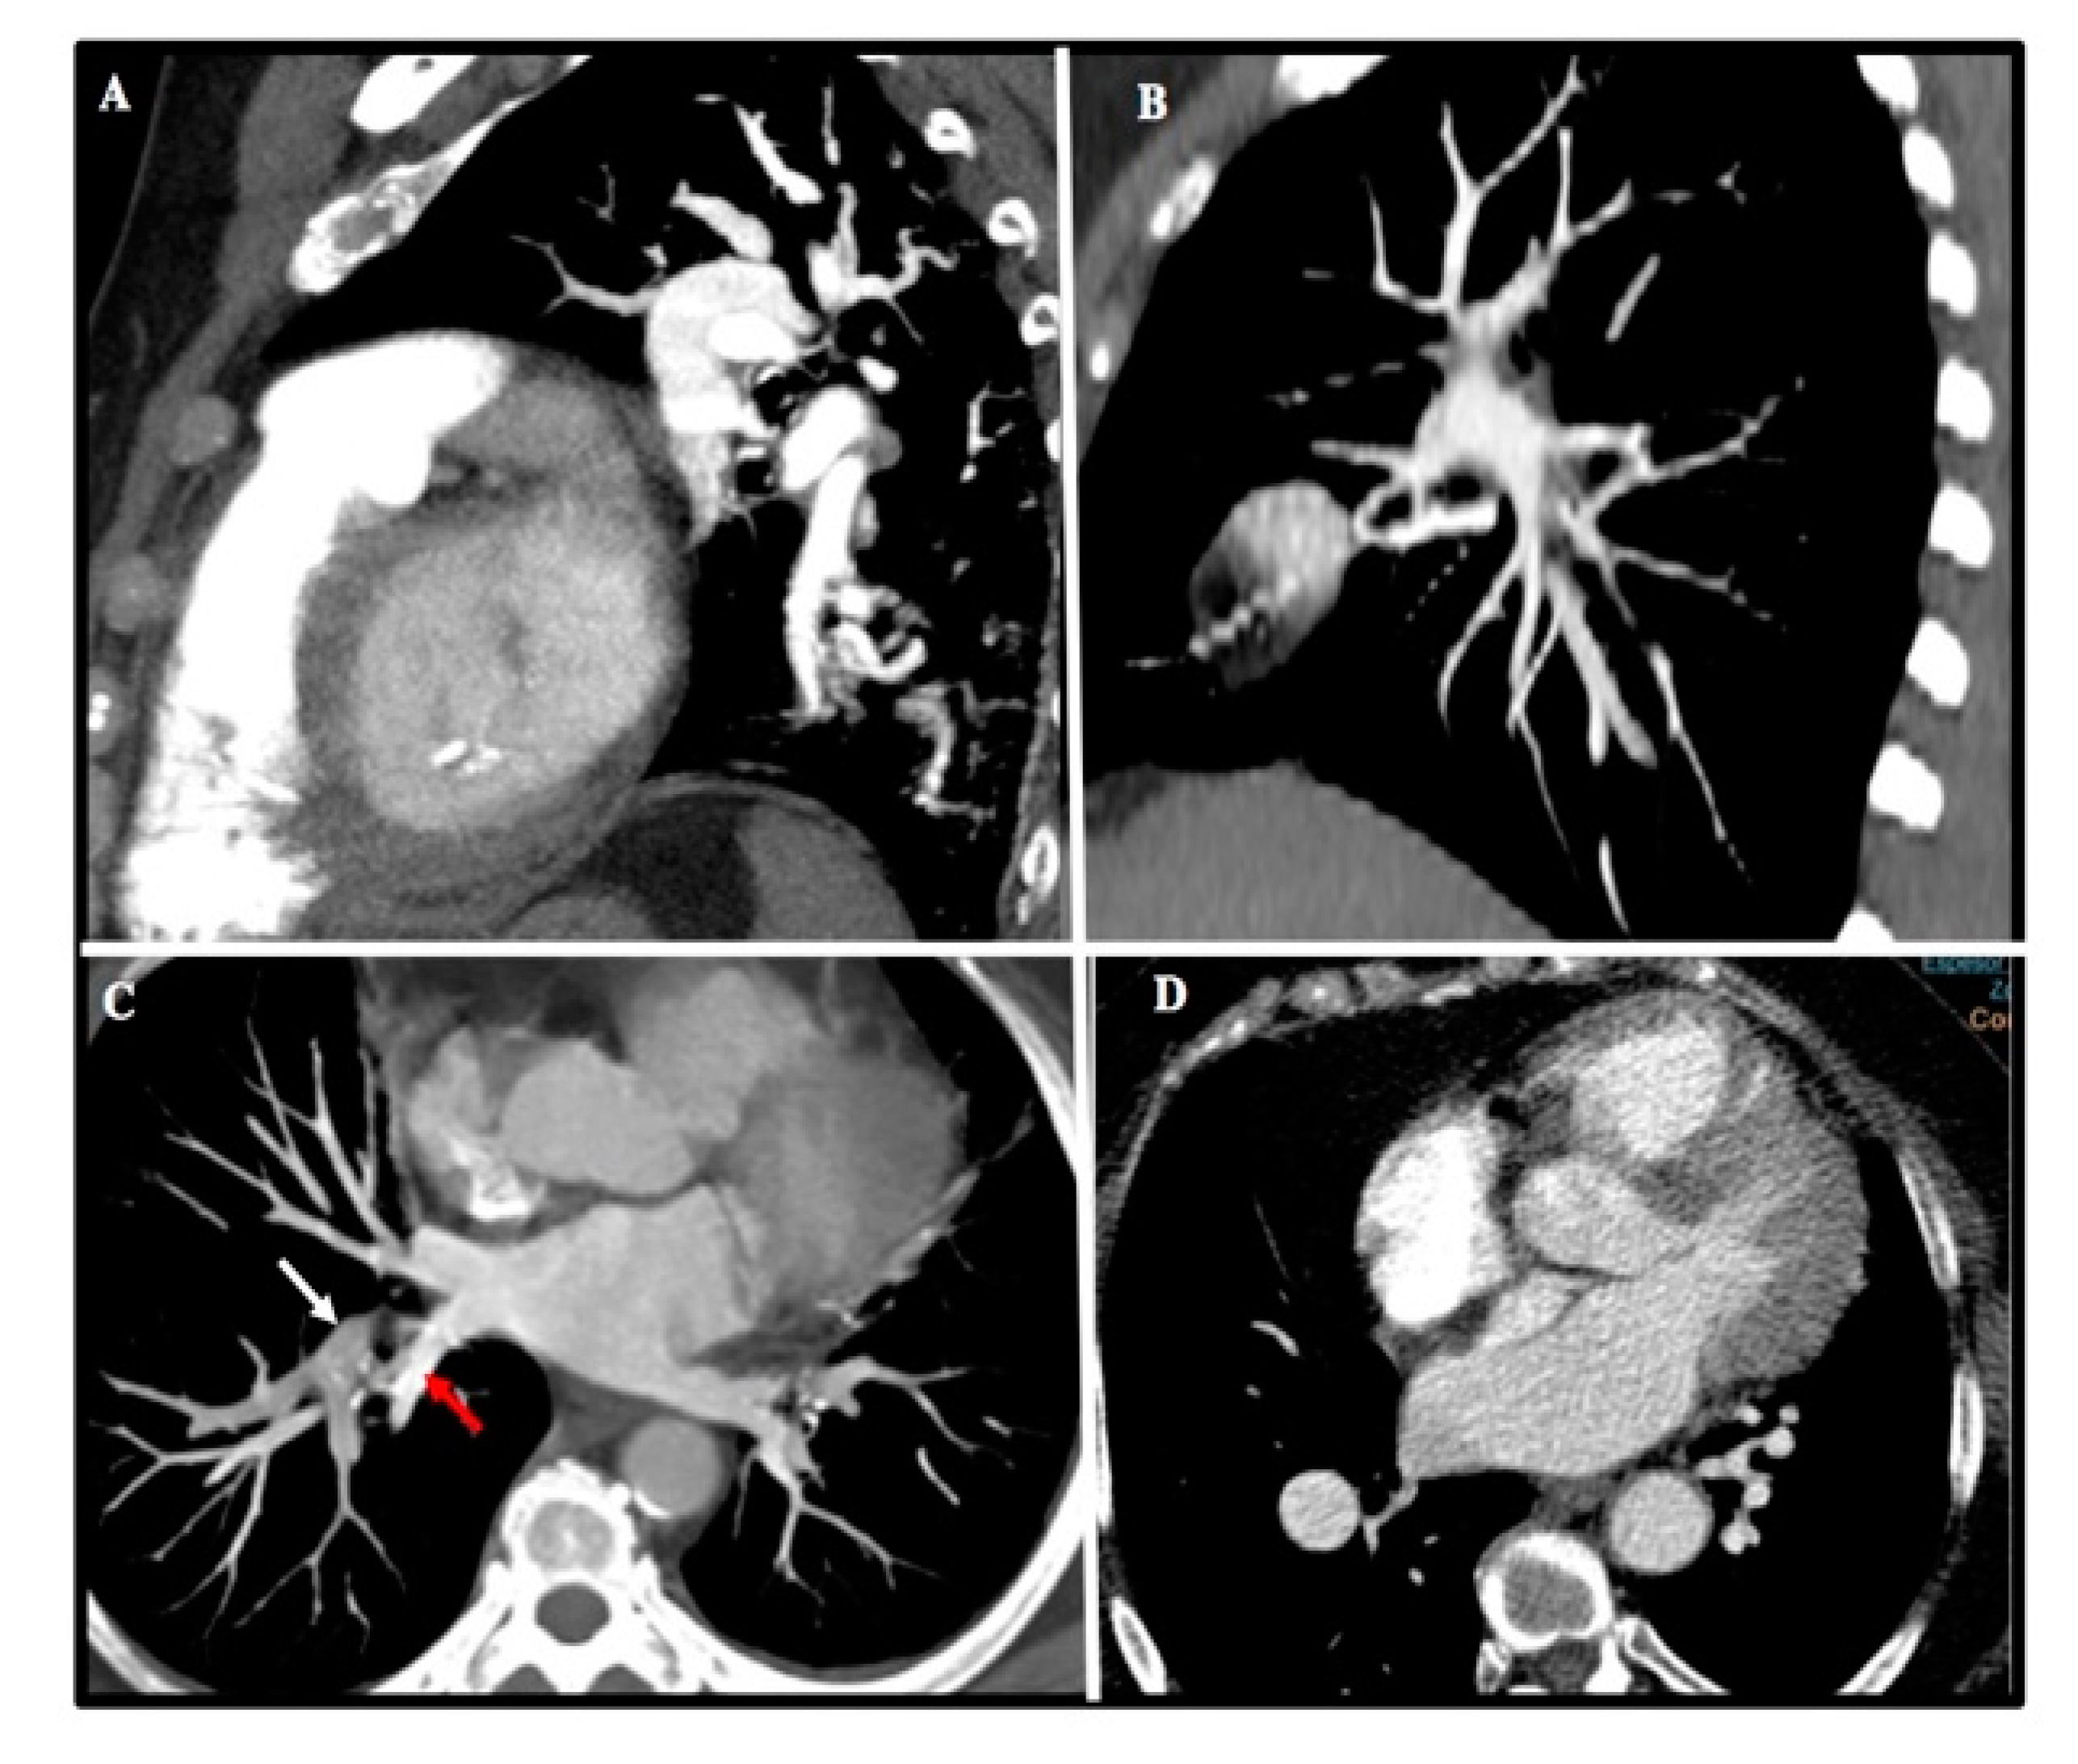

Up to 89% of MCTA studies were considered optimal. The most frequent causes of suboptimal studies were slice thickness greater than 3 mm (38%), poor opacification (25%), respiratory motion artifact (11%), obesity (9%), and improper breath-holding (9%) (Figure 2).

Figure 2.

Common imagen artifacts found in MCTA. (A) Motion artifact at lower lobes. (B) CT stair artifact due to inadequate slice thickness. (C) Suboptimal contrast opacification of right upper lobe artery (white arrow) and inferior right vein (red arrow). (D) CT image noise in an obese patient.